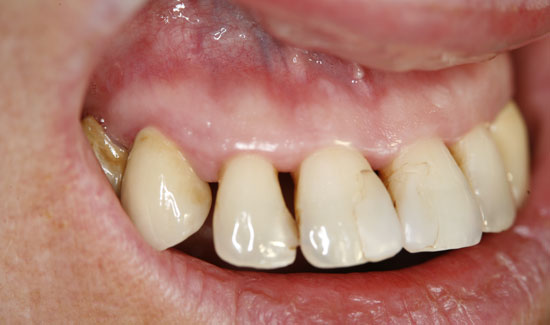

Фиг. 2: Клиничен аспект на зоната 1-2, образуване на мехурчета по възпалената тъкан. Непрекъснато всмукване в близост до зоната на употреба.